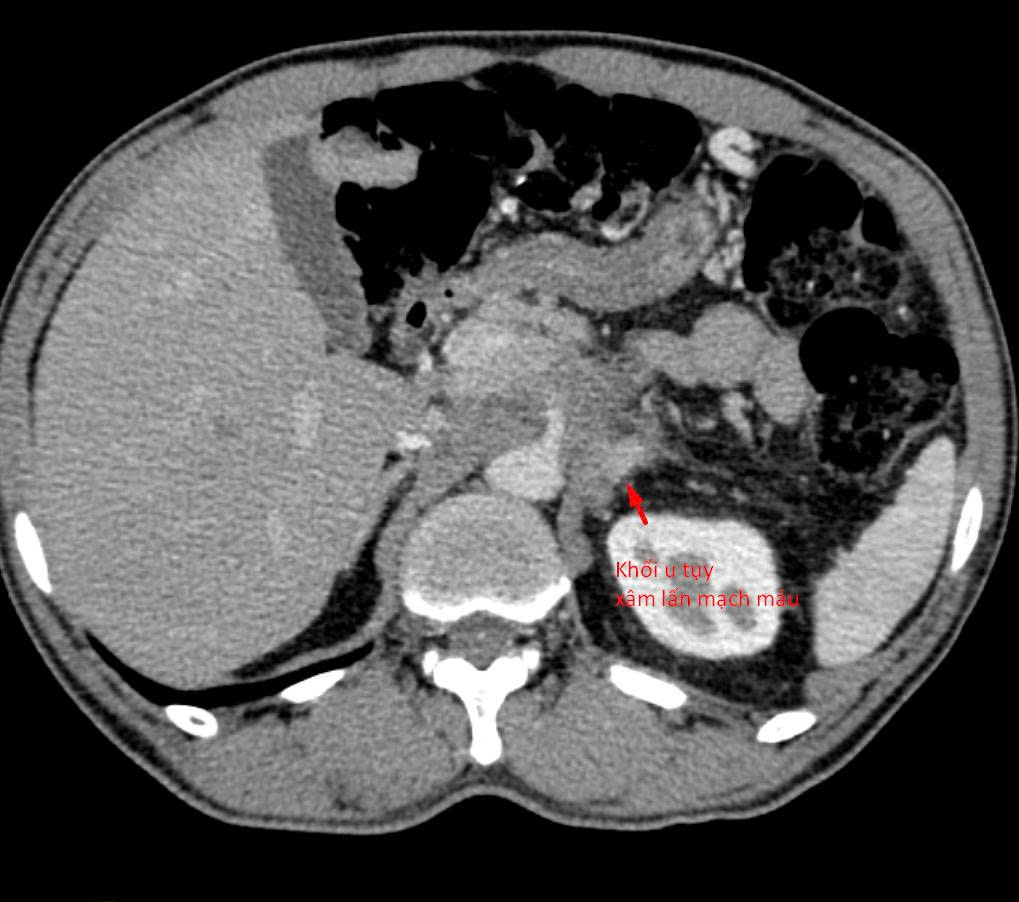

Bệnh nhân 64 tuổi (tại Hà Nội) có khối u tụy xâm lấn mạch máu được chẩn đoán tại nhiều bệnh viện khác nhau. Tuy nhiên, do khối u nằm ở vị trí đặc biệt phức tạp, áp sát nhiều cấu trúc nguy hiểm, các bác sĩ chưa thể tiến hành sinh thiết để xác định mô bệnh học – bước then chốt quyết định hướng điều trị ung thư.

Khối u tủy xâm lấn mạch máu.

Sau khi tiếp nhận bệnh nhân, các bác sĩ đã tiến hành đánh giá lại toàn bộ cấu trúc giải phẫu và đường tiếp cận khối u. Hầu hết các hướng sinh thiết thông thường đều không khả thi do nguy cơ tổn thương mạch máu lớn và các tạng quan trọng.

“Chúng tôi chỉ còn một ‘khe cửa hẹp’ duy nhất: tiếp cận từ phía sau, xuyên qua khoảng giữa cột sống và thận. Đây là đường vào rất khó, rủi ro cao và đòi hỏi kỹ thuật can thiệp cực kỳ tinh vi”, bác sĩ Giang chia sẻ.

Dưới hướng dẫn của CT đa dãy độ phân giải cao, mũi kim sinh thiết được đưa chính xác qua khe an toàn duy nhất, tiếp cận khối u và lấy mẫu bệnh phẩm thành công. Thủ thuật diễn ra an toàn, không ghi nhận biến chứng, mẫu mô đạt yêu cầu để phục vụ chẩn đoán.